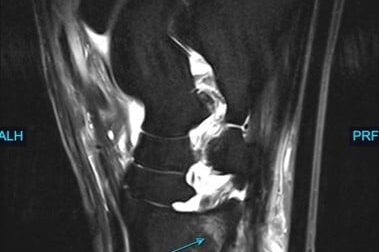

Copper is a 4 year female old Shih Tzu who had a history of elevated liver enzymes. Copper’s ALT was 700 (rr 0-120), pre bile acids were 84.7 (rr <13), and post bile acids were 256.4 (rr <25). With these lab values, the referring veterinarian was concerned for a possible shunt and Copper was referred to Animal Imaging.